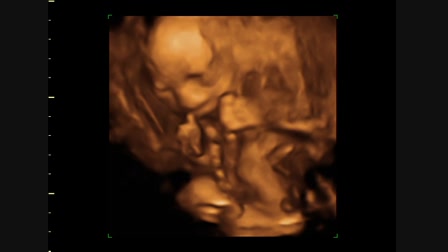

Hédi forog 2